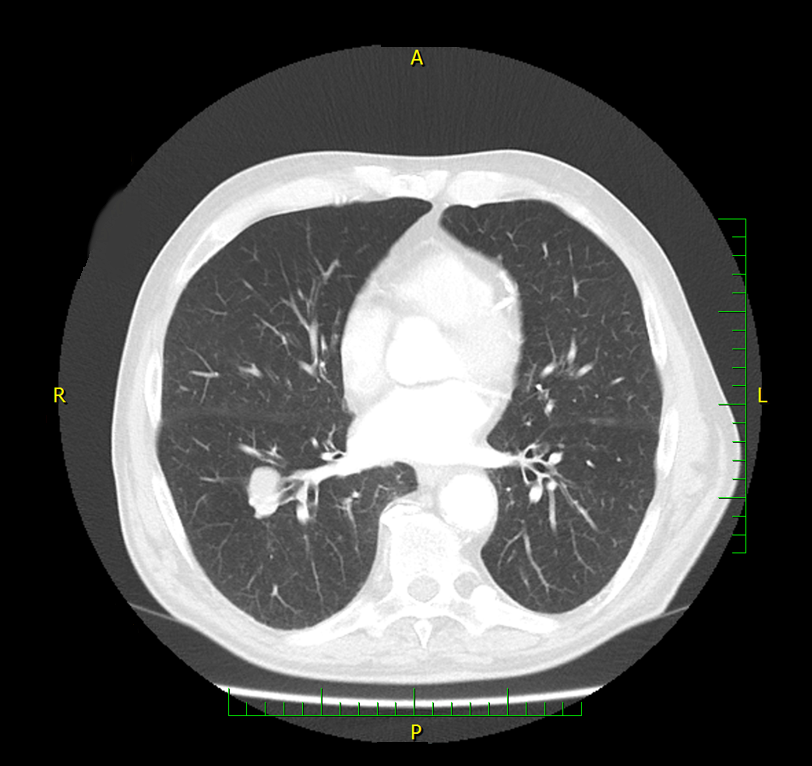

Do vaší ordinace vchází Milan Drahoš. Než se padesátiletý, velmi obézní muž dostane ode dveří k vámi nabízené židli, zadýchá se. Podle CT hrudníku, který si s sebou pacient přináší, má zvětšené uzliny v oblasti mediastina. Snímek odhaluje také mnohočetná ložiska plic. Není na co čekat, je třeba co nejrychleji zahájit léčbu. Ujmete se tohoto případu?